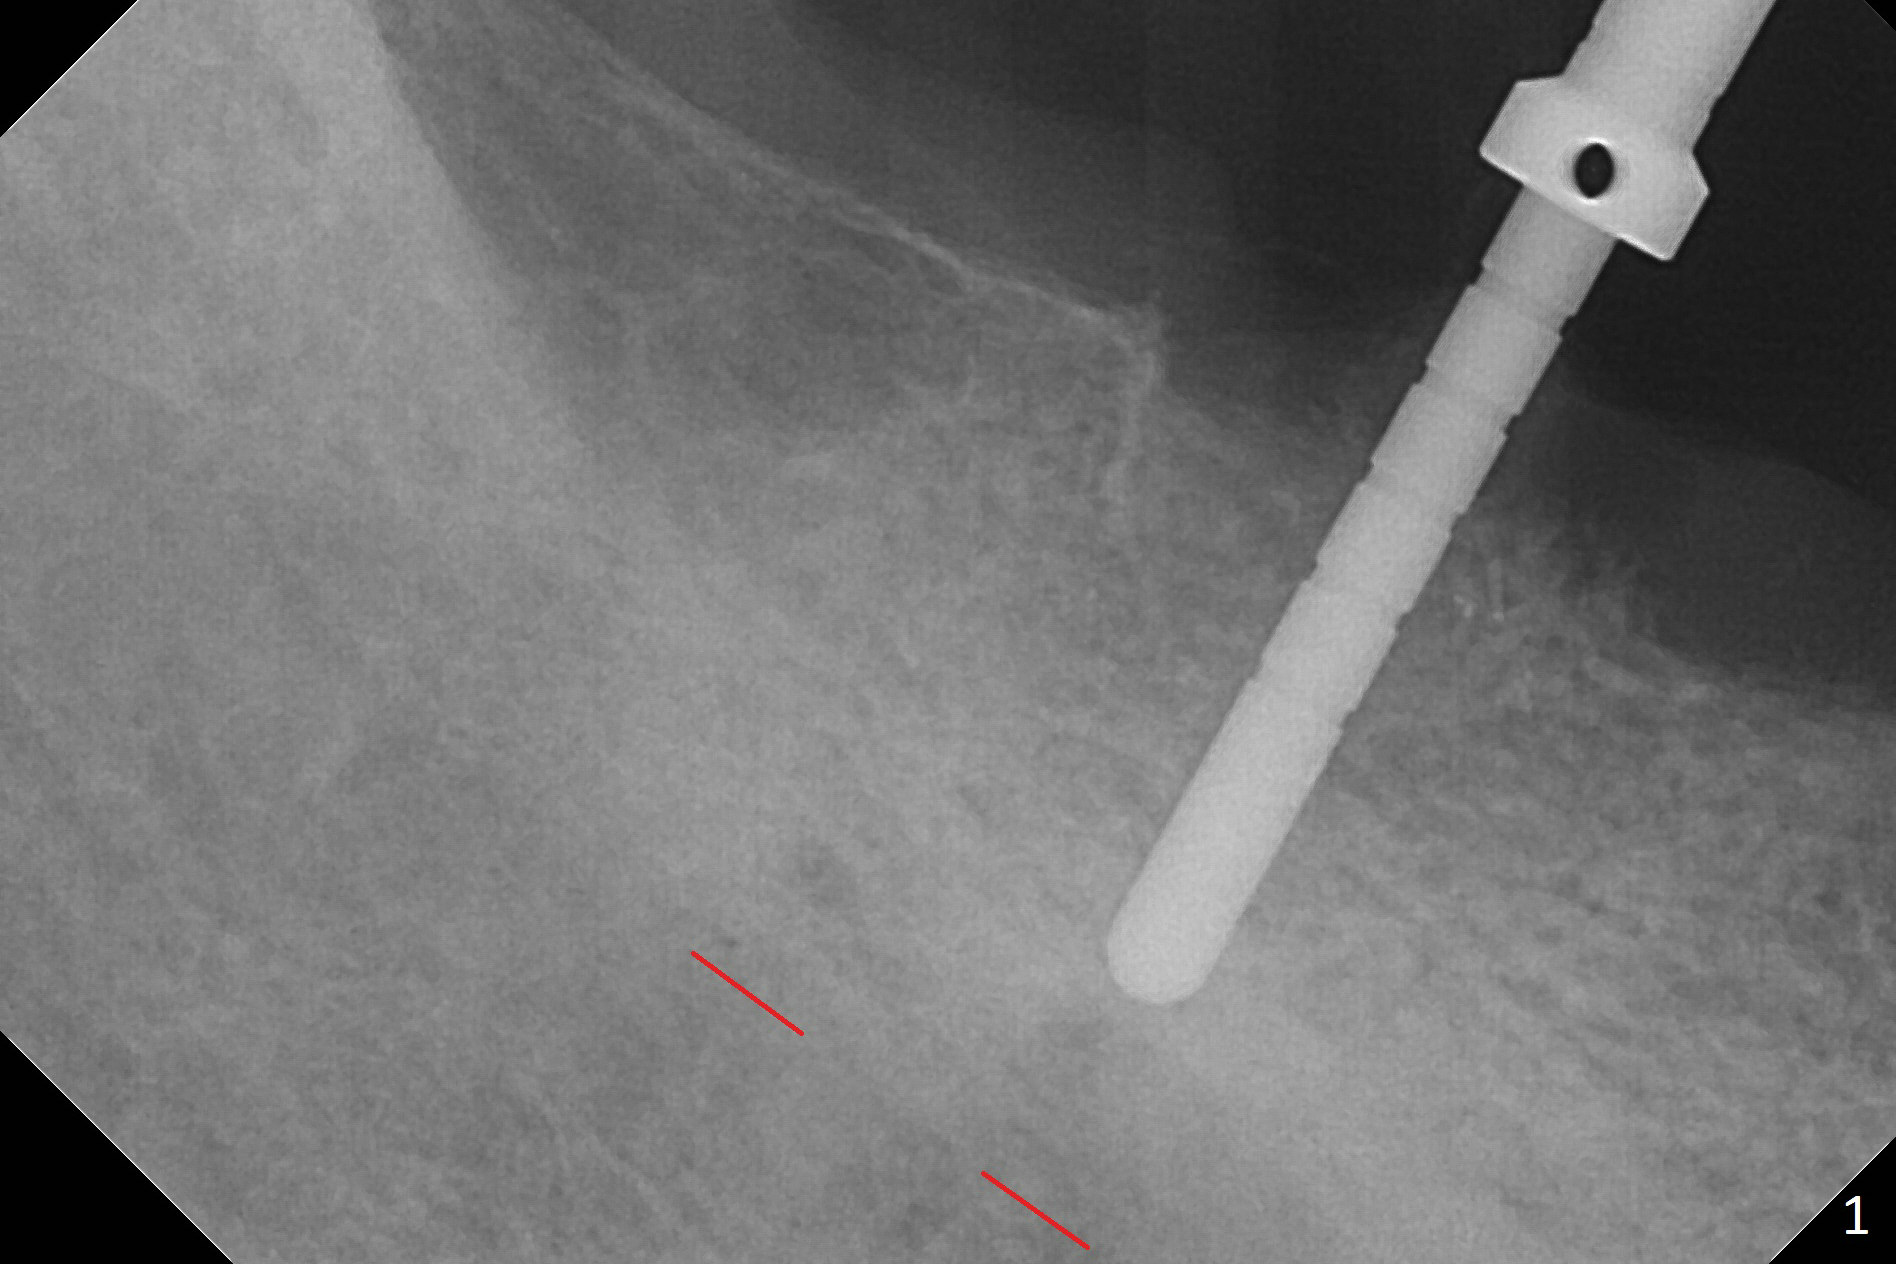

There are 2 challenges associated with #31 implant placement: indistinct Inferior Alveolar Canal (Fig.1-4) and difficulty in fabrication of a provisional (Fig.5).  After placing a 5.5x13 mm implant (Fig.3 supracrestal (<)), it is removed for apical resection for ~ 2 mm; when it is reseated, it is subcrestal (Fig.5 <).  A simplified temporary provisional (Fig.5 P) is fabricated around a 6.5x4(4) mm abutment (A) without adapting the lower RPD.  The patient is advised not to wear the latter.  When the socket heals, there will be 2 options: no provisional or a new one.  The latter should have good retention to the abutment and no contact with the lower RPD in and out.